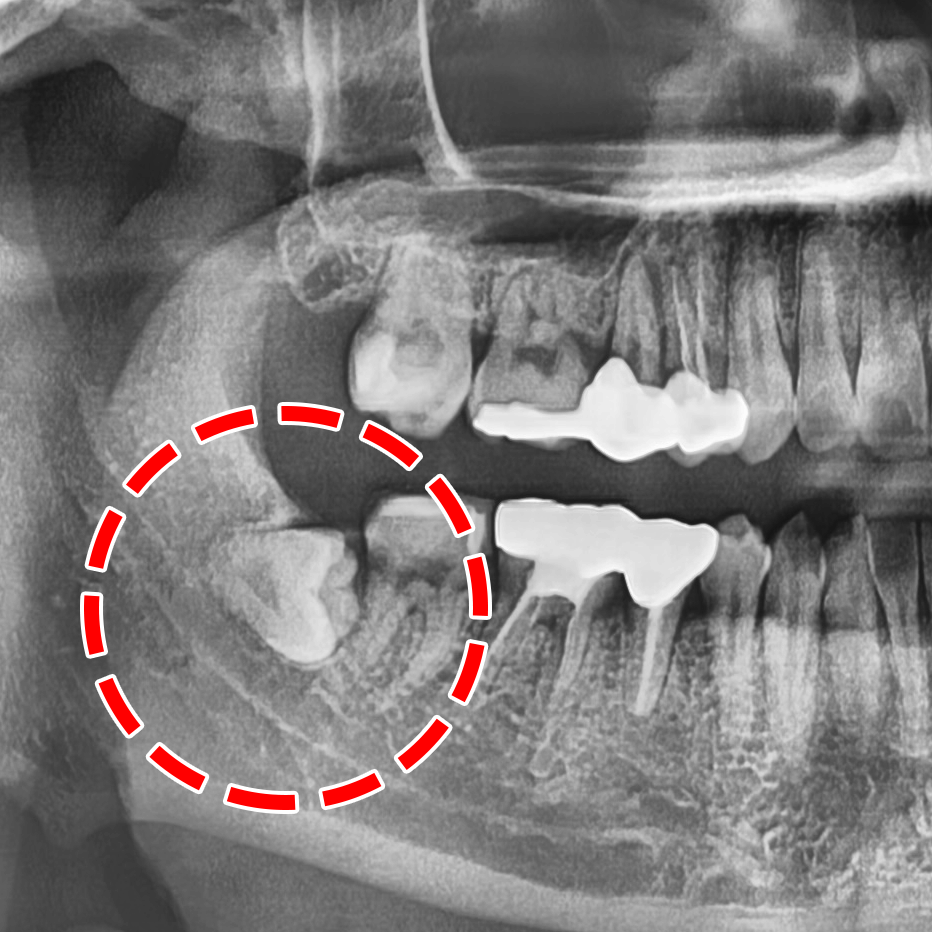

특히 똑바로 나지 않거나 부분적으로 맹출되었을 때

세균이 쉽게 번식해 충치, 잇몸 염증, 주위 치아 손상 등

구강 질환을 쉽게 일으킬 수 있습니다.

누워 자라거나 잇몸 속에 숨어있거나 일부만 나왔을 때

사랑니 뿐만이 아닌 인접 치아까지 충치가 퍼질 수 있을 때

사랑니 발치는 사전에 정확한 검사를 통해

섬세한 계획을 수립하고 나서 이뤄지는데요.

특히 위쪽은 상악동을,

아래쪽은 신경을 주의해야 됩니다.

이를 뽑는 과정에서 잘못 건드렸다가 상악동 천공

또는 신경을 건드려 일시적인 마비 증상이 나타날 수 있습니다.

그러므로 치근(치아의 뿌리)과

상악동막, 신경과의 거리가 얼마나 되는지

세밀한 분석이 이뤄져야 됩니다.